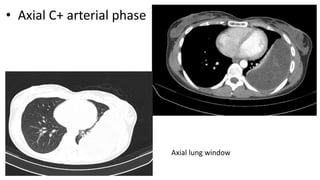

• Axial C+ arterial phase

Axial lung window

•A well-defined oval shaped large intra-pleural cystic lesion with numerous daughter cysts

inside is seen in the left side of the chest. It showed fluid CT density, smooth margin,

hypodense content relative to the capsule with a thin enhancing capsule, picture highly in

favor of an uncomplicated pleural hydatid cyst.

Both lungs clear with normal pulmonary vascular markings, no focal lesion.

Normal mediastinum with normal mediastinal vasculature, no mass or enlarged LN.

• Axial C+arterial phase Axial lung window